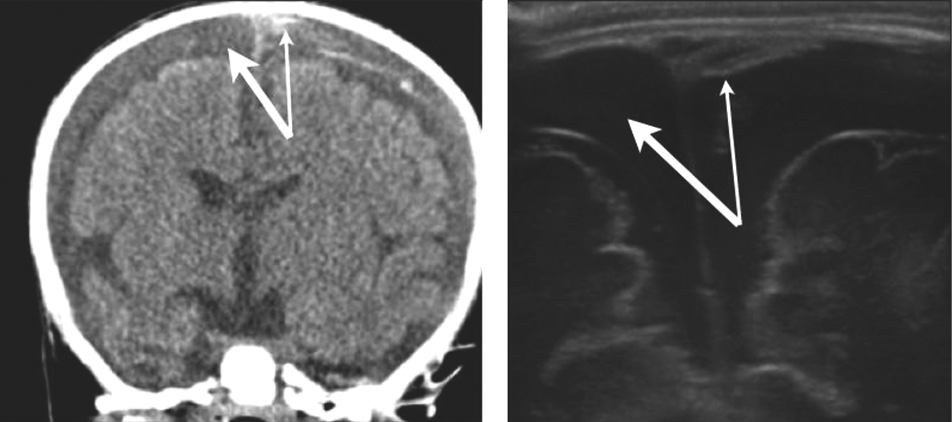

Bu konuda yapılmış güzel bir çalışmayı örnek gösterelim. McCormick ve ark.’nın 2015 te yayınlanmış prospektif çalışmalarına, BT ile kafa içi kanama saptanmış, pediatrik kafa travmalı hastalardahil edilmiş. Tüm hastalara acil hekimi tarafından intrakraniyal USG ile görüntüleme yapılıp, görüntüler video klip olarak kayıt edilmiş. Hastaların tanı ve klinik durumlarına kör olan ve ultrason konusunda eğitimli iki bağımsız acil doktorundan, bu video klipleri izleyip İKK var veya yok şeklinde yorum yapmaları istenmiş.

Çalışmaya 12 hasta dahil edilmiş. 4 hastada İKK varmış, diğer 8 hasta ise kontrol grubu olarak alınmış. Birinci gözlemci İKK’yı %100 duyarlı ve % 100 özgüllük ile belirlerken, ikinci gözlemcinin duyarlılığı %50 ve özgüllüğü %87.5’ miş. Gözlemciler arasındaki anlaşma oranı %75 olarak bulunmuş. Bu gözlemciler ultrason konusunda eğitildikleri halde daha önce hiç intrakraniyal USG deneyimi olmayan doktorlarmış.

Çalışmadaki kısıtlılıklara rağmen USG konusunda eğitimli bir acil doktorunun kraniyal USG ile İKK’yı belirleyebileceği gösterilmiş ve yeterli teorik ve pratiğe sahip bir doktorun İKK’yı başarıyla belirleyebileceğine kanaat getirilmiş.